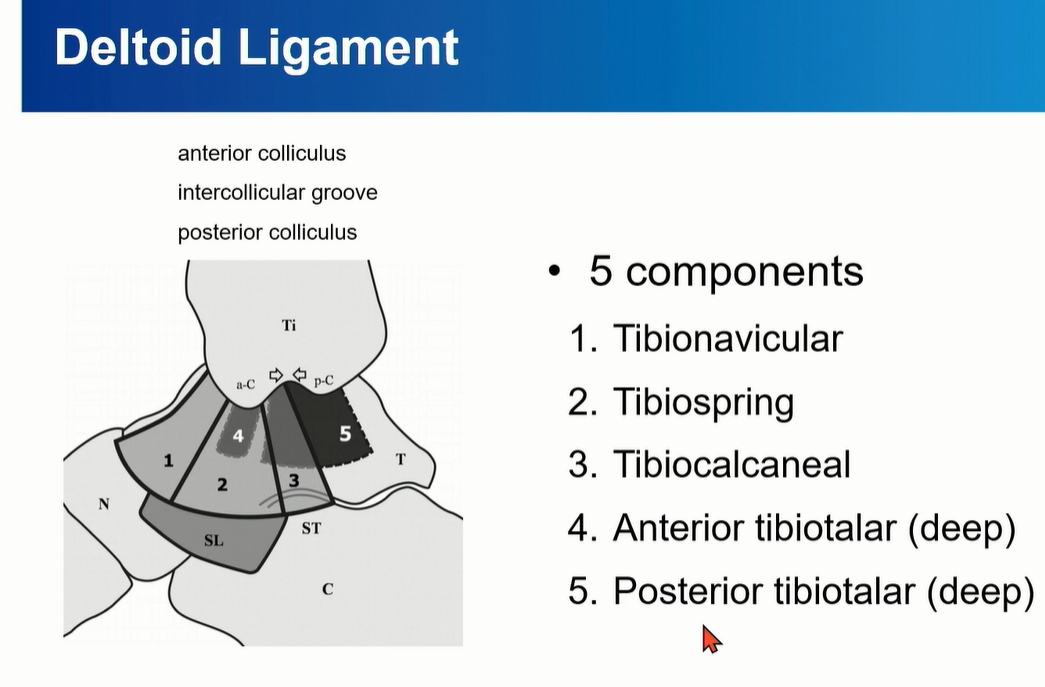

3. Deltoid ligament

Superfical Deltoid ligament: 1-3

Deep Deltoid ligament: 4-5

Superficial은 사실상 연속적인 구조로 되어 있다. 구분은 인위적.